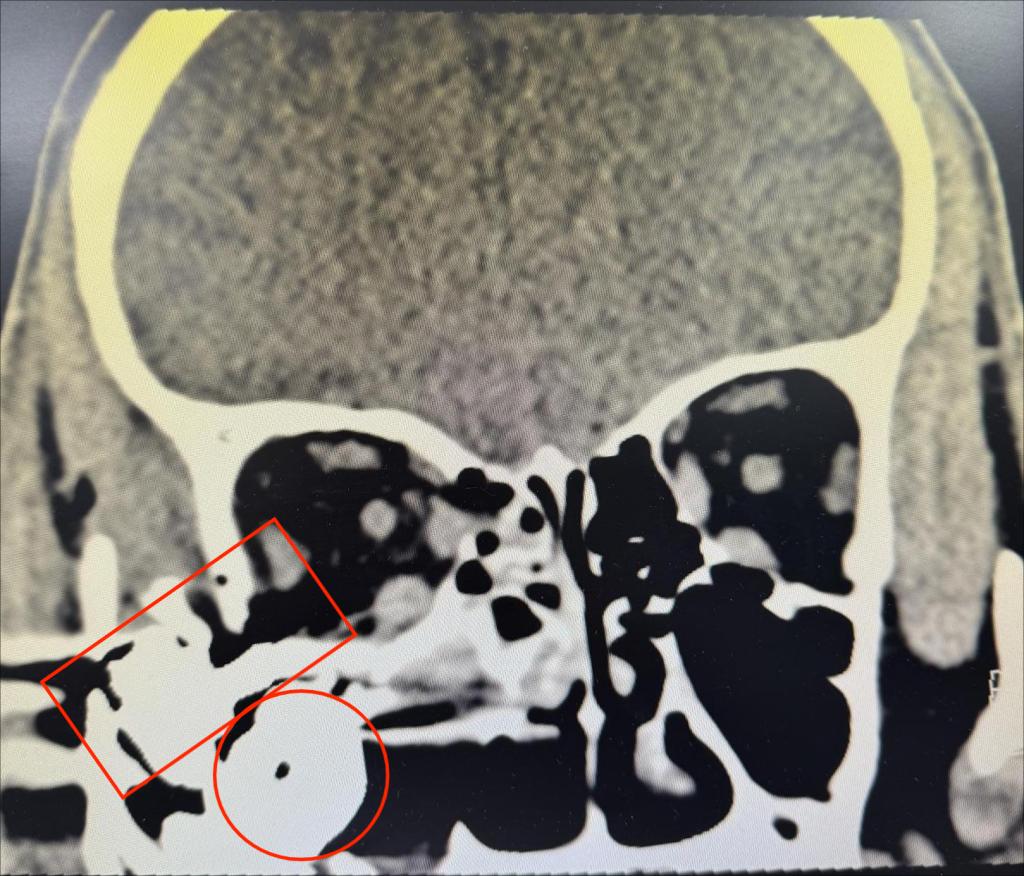

晚上九点多患者赶到医院,一直在病房等候的眼整形眼眶泪器病专业组长刘子瑶副教授、值班医生王艳芬、病房护士及手术室护士已经做好了各项准备,眼外伤急诊绿色通道畅通,1小时后患者已完成必要术前检查及准备,安然躺在了手术台上。经过仔细消毒冲洗探查伤口,主刀医生刘子瑶不禁捏了把汗,患者右眼睑皮肤全层破碎不堪,上下泪小管断裂,伤口深达眶骨,伤口内散在树枝、尘土等大量异物,面部皮肤满布黑色点状异物,眼球破裂,眼内容物大部分已流失,眼球结构已不成形。眼眶CT显示眶内及上颌窦内有巨大金属异物,但在探查过程中眼眶内无法探及异物。刘子瑶副教授像拼拼图一般,仔细辨认、对位破碎的眼睑结构,寻找到针尖大小的上下泪小管断端,精细缝合,经过3小时余的努力,成功吻合了泪小管,恢复了眼睑正常的外形,并清理了残余眼内容物,保留好巩膜、结膜结构,为二期安装义眼台做好准备。

眼眶CT显示异物位置(图2)

术后给予患者抗感染治疗的同时,刘子瑶副教授反复观察CT影像,考虑如此巨大的金属异物是如何进入眼眶和上颌窦的,又该如何在最小损伤的情况下将其取出呢。经与耳鼻喉科共同商议,异物取出手术定在5天后两科共同协作完成,耳鼻喉科由王波涛医生主刀,设计巧妙的口内唇龈沟切口,避免面部遗留手术痕迹,从上颌窦底部向上分离探查,终于顺利取出巨大圆柱形金属异物1枚,但与CT显示形状比对,应该还有另一块不规则形异物并突入眼眶内,继续由上颌窦底部向眶底探查,果然成功取出第二枚异物,这枚异物基底成圆柱形,底座上延伸出长约3厘米的突起,突入眶内。异物取尽后,刘子瑶医生为患者安装了义眼台,成形好结膜囊,静待恢复。时至现在,患者悬着的心终于落下,不再惊魂未定的他才愿意回忆并向医生讲述那天的爆炸伤,强大的冲击力使得巨大的金属异物打破眼睑、穿过眼球及眼眶,停在上颌窦内。目前患者已平稳出院,伤情恢复良好,眼部外观满意。